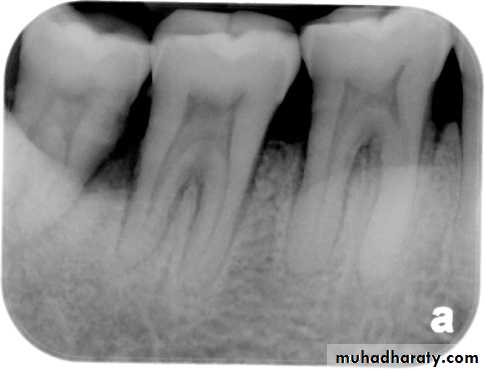

– Radiolucent enlargement of pulp canal

– Original root canal outline distorted

– Bone changes are seen only when root perforation into periodontal ligament takes place.